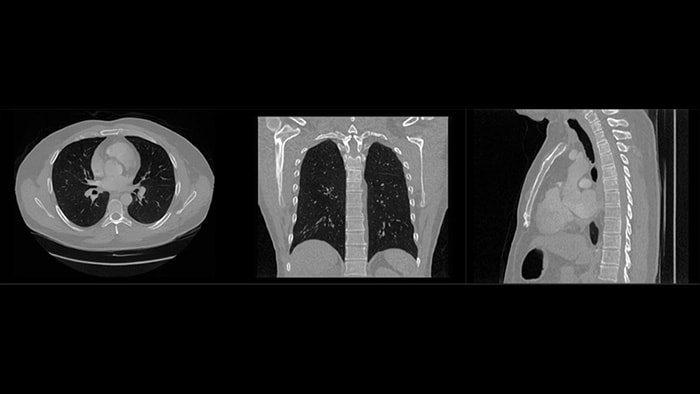

Whether we are creating an easier-to-use ultrasound, making a patient monitor interface more intuitive, or providing clinical insights that help a radiologist arrive at a more confident diagnosis faster, our solutions are designed to help make your care delivery more efficient and effective.